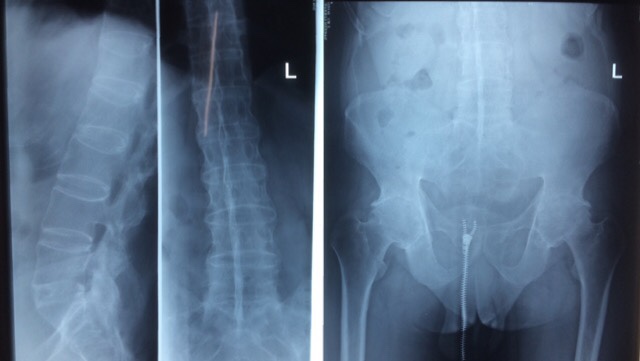

辅助检查:颈、胸段脊柱向右侧倾斜,腰段脊在向左倒倾斜,生理弯曲度变直、颈、胸、腰椎各椎体呈竹节样改变,骨质呈疏松征象,颈、胸、腰椎各椎间隙及椎小关节 关节不同程度变窄、消失。骶髂关节模糊,双髋关节关节周围诸骨不同程度骨质增生改变,骶髂及双髋关节间隙变窄、消失。